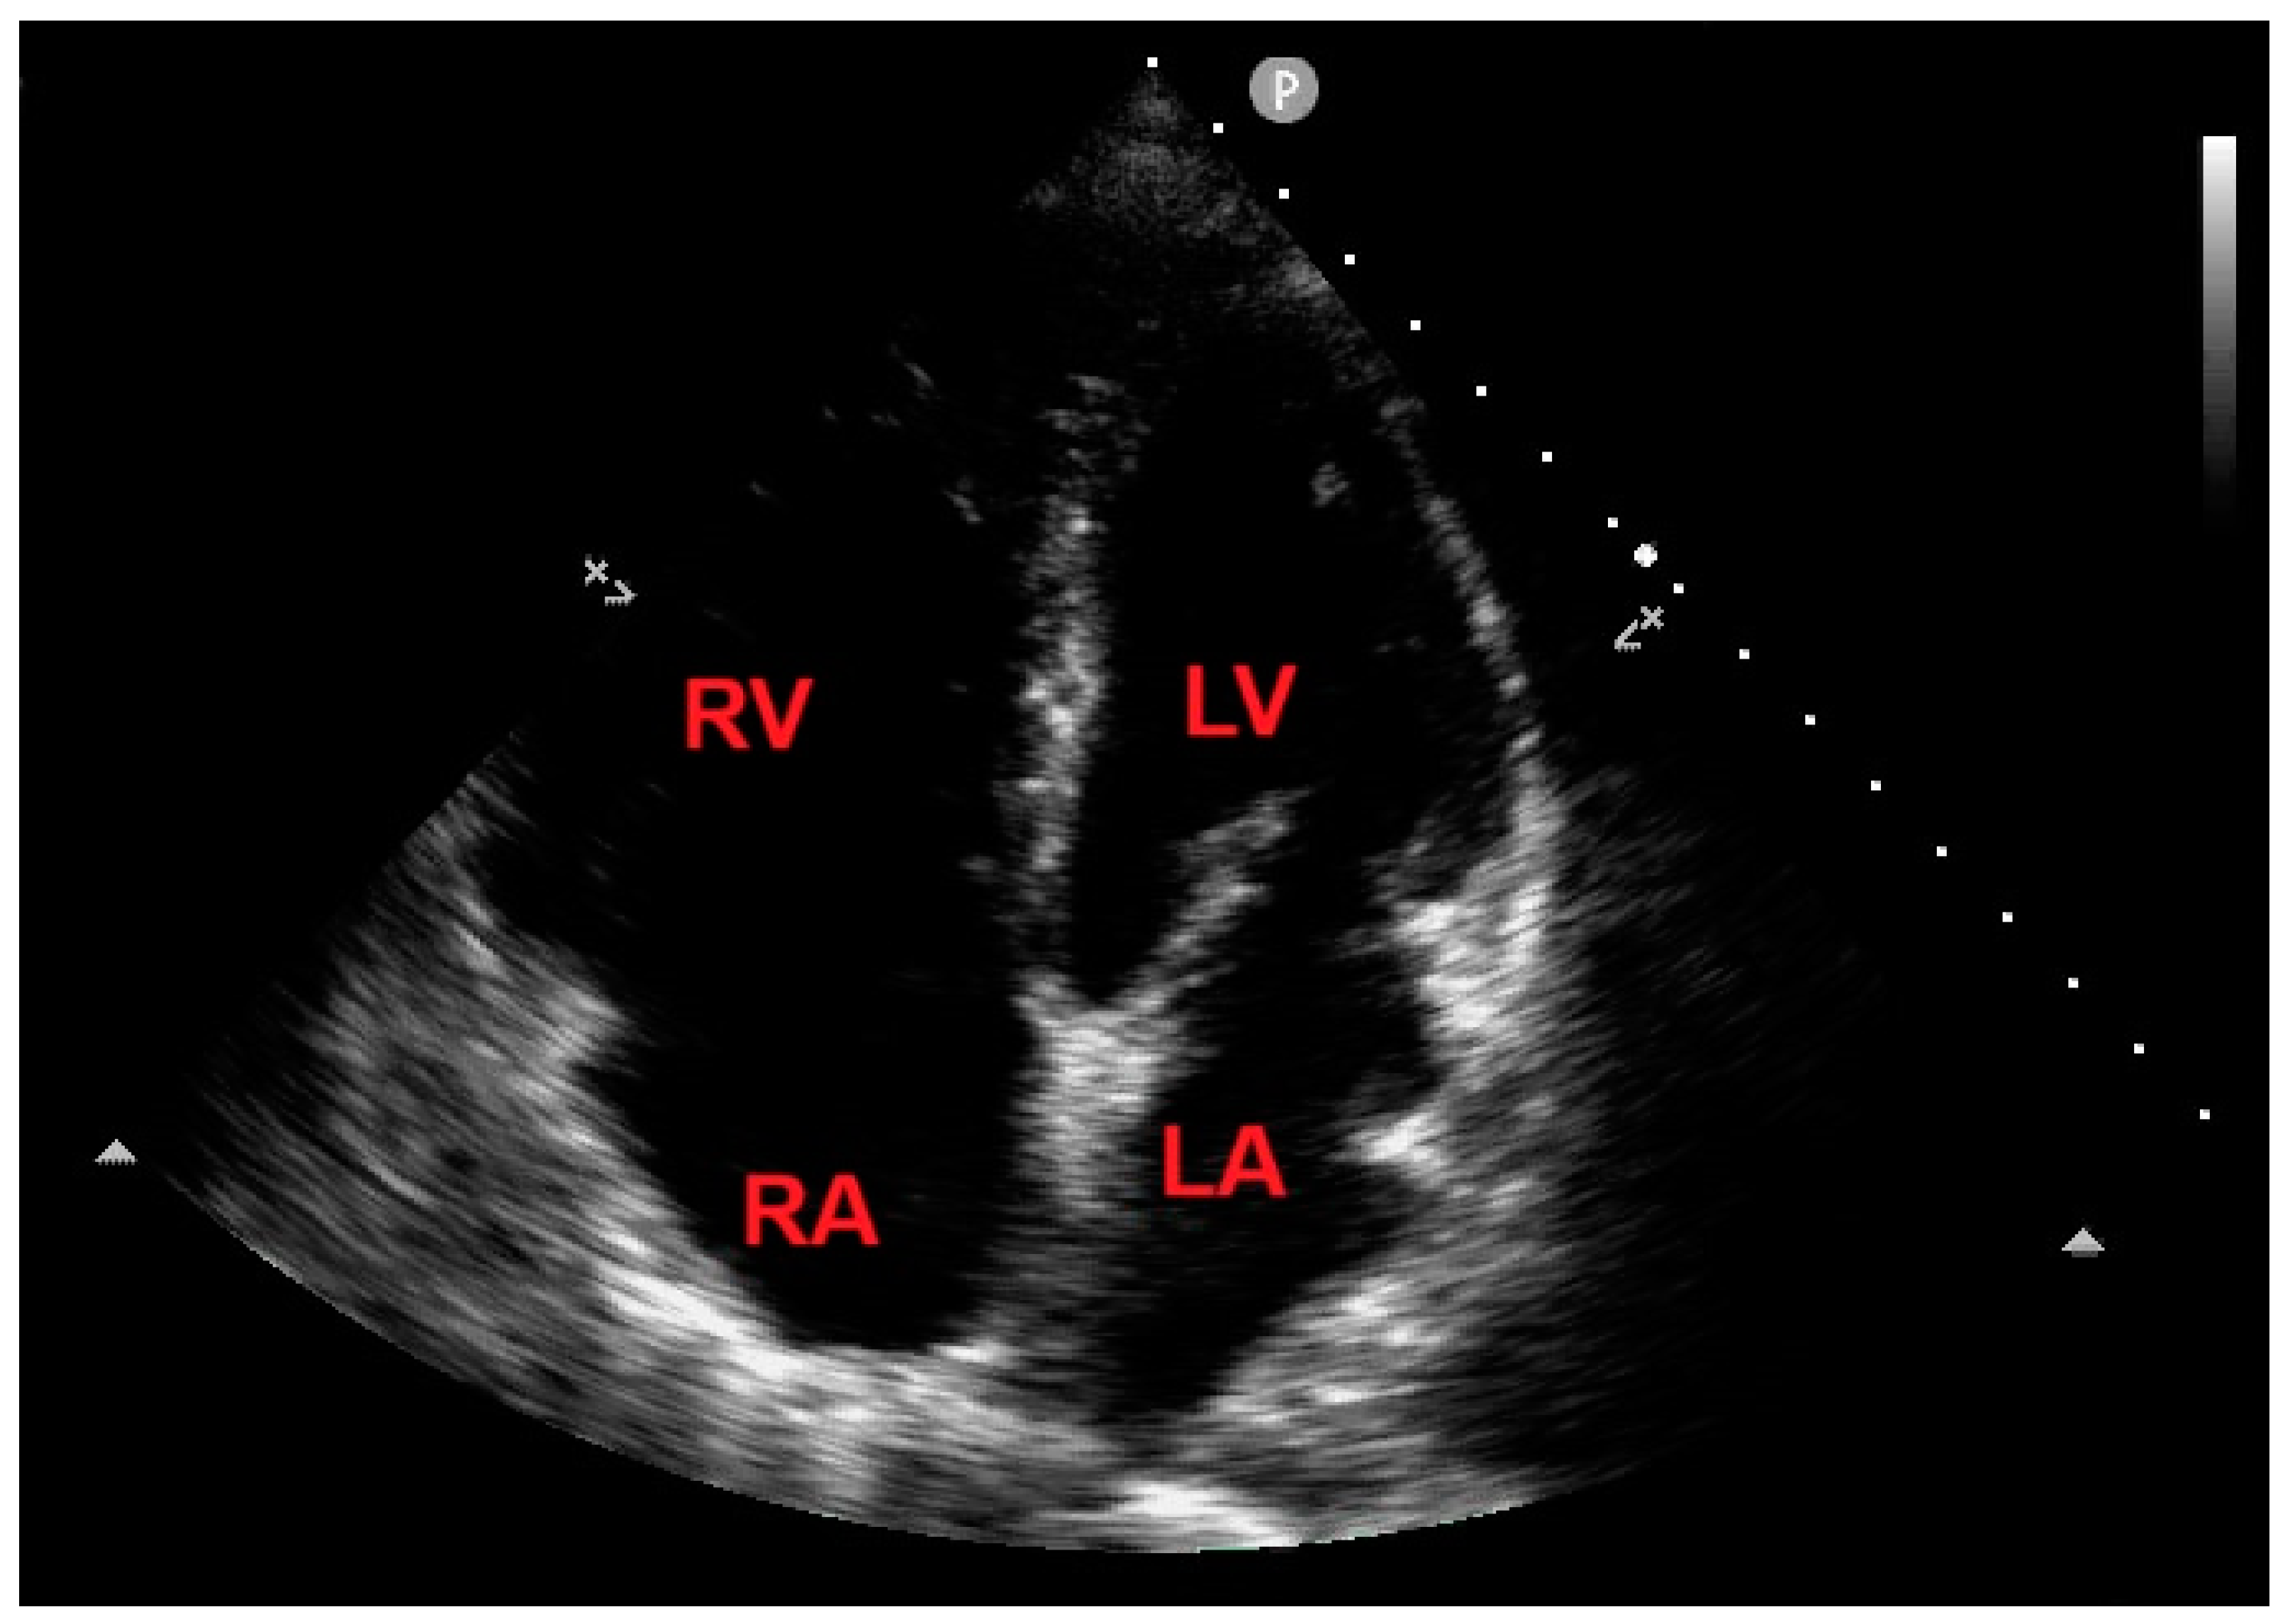

An urgent bedside echocardiogram highlighted a significant dilatation of right-sided cardiac chambers (RV to left ventricular basal diameter ratio = 2.4; RV inflow tract diameter = 60 mm), RV hypertrophy (RV free wall thickness = 10 mm) and mild hypokinesia of the RV lateral wall, as assessed by tricuspid annular plane systolic excursion (TAPSE) magnitude (17 mm); a moderate tricuspid regurgitation was present. The peak tricuspid regurgitation velocity (TRV) was 3.4 m/s, indicating high probability of pulmonary hypertension (PH); the inferior vena cava was significantly dilated (transverse diameter = 2.8 cm), with inspiratory excursions <50%; accordingly, the estimated systolic pulmonary artery pressure (sPAP) was 60 mmHg. On RV focused apical four-chamber view, a large sessile echogenic formation with hyperechoic edges (size 3.9 cm x 2.6 cm), attached to the mid-apical portion of the RV free wall, protruding into the RV cavity, was detected (Figure 3, A and B). By placing a 5 mm sample volume of pulsed wave (PW)-tissue Doppler imaging (TDI) at the level of the mobile portion of RV mass, a RV mass peak antegrade velocity (Va) of 13 cm/s was obtained; moreover, on PW-TDI, the RV mass showed a pattern of incoherent motion, totally discordant and independent from the surrounding myocardial tissue (Figure 3C).

Figure 3. Transthoracic echocardiography. Right ventricular focused apical four-chamber view. (A) Large sessile echogenic formation with hyperechoic edges (red arrow), attached to the mid-apical portion of the right ventricular free wall, protruding into the RV cavity. (B) Measurement of the right ventricular mass size. (C) Assessment of the right ventricular mass peak antegrade velocity by pulsed wave tissue Doppler imaging. The right ventricular mass showed a pattern of incoherent motion, totally discordant and independent from the surrounding myocardial tissue. LA, left atrium; LV, left ventricle; RA, right atrium; RV, right ventricle. The symbol * indicates the right ventricular mass peak antegrade velocity.

Figure 8. Transthoracic echocardiography. Apical four chamber view, demonstrating the total disappearance of the right ventricular mass. LA, left atrium; LV, left ventricle; RA, right atrium; RV, right ventricle.